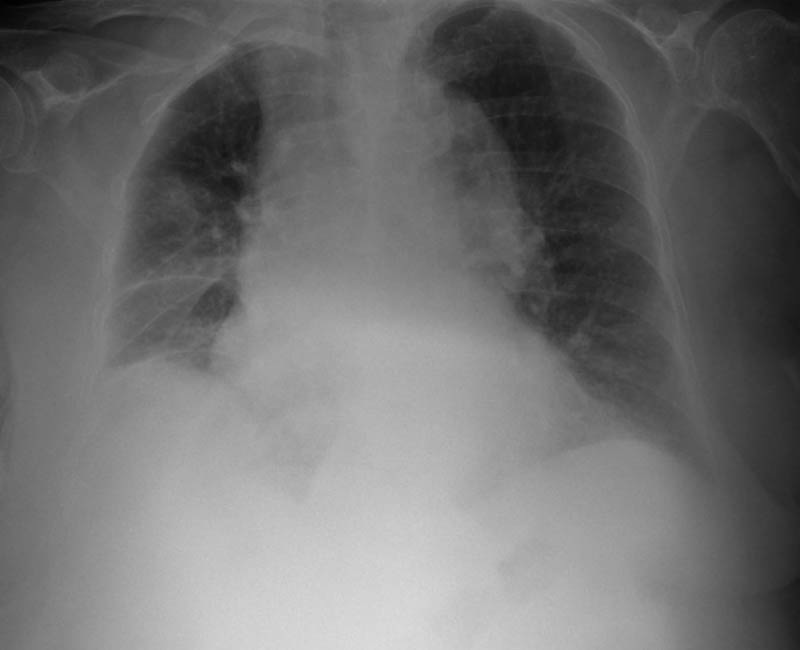

MO Distres respiratorio del adulto por trauma.